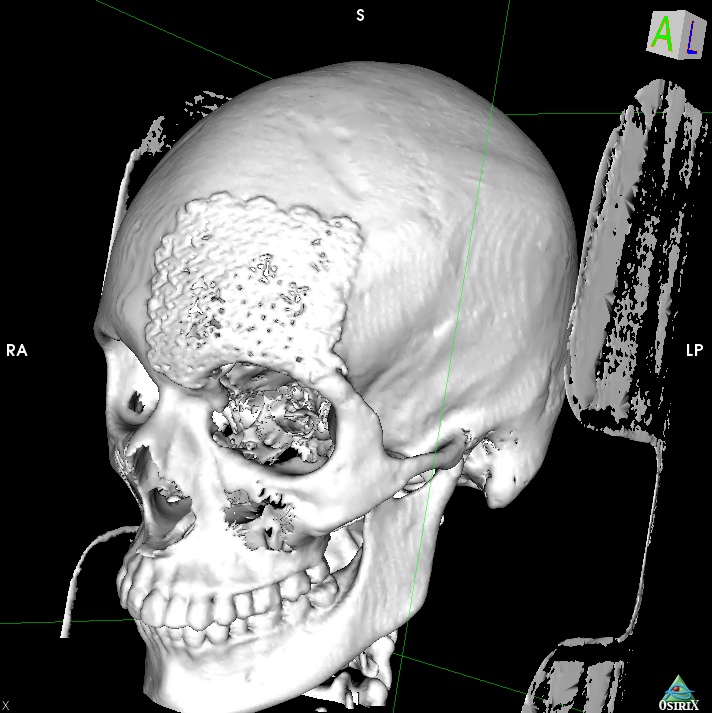

Здравствуйте!Беспокоит постоянная головная боль в области лба и в виске слева и звон в левом ухе.Боль монотонная и пульсирующаяОбезболивающие не помогают.Неврологи ставили диагноз мигрень,делал уколы иринекс,пил таблетки от мигрени ,ничего не помогает.Также лечили внутричерепное давление тоже не помогло(пирацетам,магнезий,актовегин,диакарб)В левой височной области имеется архоинодальная киста 36х10х17 мм.Также расширены периневральные пространства зрительных нервов.Глазное давление в нормеМожет ли данная киста быть причиной головной боли ?

Снимки мртhttps://drive.google.com/file/d/1sbWERelK3rUJm4z0P7nltAPZVu9NX0md/view?usp=drivesdk

Здравствуйте!Прикрепил заключение. Не пойму как полностью отправить сами снимки МРТ Может сможете через Mail облако посмотреть https://cloud.mail.ru/public/9f6x/xjqpBSKLt